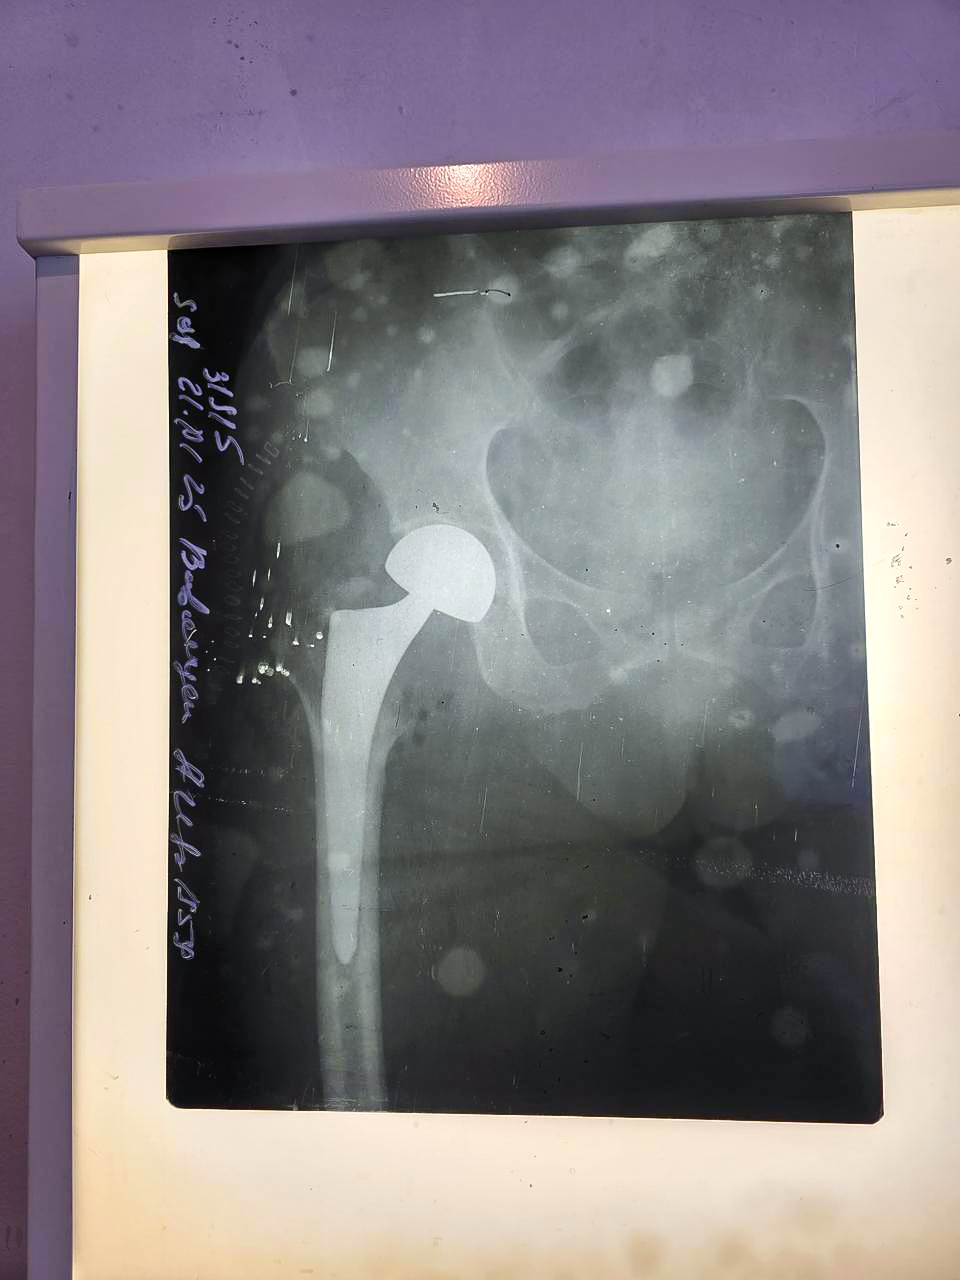

ERAmedia xəbər verir ki, bu gündən etibarən Sabunçu Tibb Mərkəzində də endoprotez əməliyyatlarının icrasına başlanılıb. Tibb mərkəzində ilk dəfə icra olunan endoprotez əməliyyatı uğurla başa çatıb.

66 yaşlı pasiyent üzərində həyata keçirilmiş bud-çanaq oynağının total artroplastikası (endoprotez) əməliyyatı icbari tibbi sığortanın Xidmətlər Zərfi çərçivəsində qarşılanıb.

Yıxılma nəticəsində sağ bud sümüyünün boyun sınığı diaqnozu ilə müraciət edən pasiyentə müvafiq müayinələrdən sonra sağ bud sümüyünün boynunun subkapital sınığı diaqnozu təyin olunub və cərrahi əməliyyata qərar verilib.

Əməliyyat xəstəxananın Travmatologiya-ortopediya şöbəsinin müdiri, ortoped–travmatoloq Turan İskəndərzadə tərəfindən həyata keçirilib. Əməliyyatdan sonra pasiyentə zəruri tibbi xidmətlər göstərilib. Hazırda onun müalicəsi davam etdirilir, vəziyyəti stabildir.